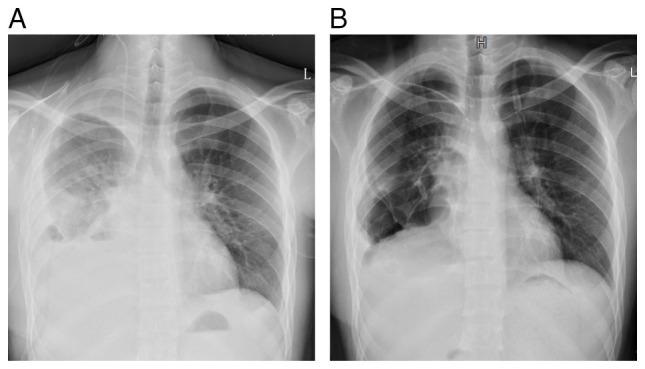

Spontaneous rupture and hemorrhage of mediastinal germ cell tumors is a rare occurrence. In the current report, the case of a 20-year-old male patient who was admitted with chest tightness and dyspnea is presented. An urgent chest CT scan revealed a large tumor in the right anterior mediastinum, measuring ~12 cm in diameter, with associated intratumoral hemorrhage. An emergency thoracotomy was performed to excise the lesion, which revealed that the bleeding was caused by a ruptured tumor. Postoperative pathological findings revealed a mediastinal mixed germ cell tumor consisting of four pathological types: Embryonal carcinoma, seminoma, yolk sac tumor and immature teratoma. Postoperatively, the patient showed marked improvement in the symptoms of dyspnea. However, the follow-up outcome was poor, and the patient succumbed 2 months after surgery. To the best of our knowledge, there are no reports of rupture and hemorrhage involving >4 mixed germ cell tumors. In the present report, the experience of the treatment of the patient is summarized, and literature was reviewed to improve clinicians' awareness of the disease.

纵隔生殖细胞肿瘤的自发性破裂和出血是一种罕见的情况。在本报告中,介绍了一名20岁男性患者因胸闷和呼吸困难入院的病例。紧急胸部CT扫描显示右前纵隔有一个大肿瘤,直径约12厘米,伴有肿瘤内出血。进行了急诊开胸手术以切除病变,结果显示出血是由肿瘤破裂引起的。术后病理结果显示为纵隔混合性生殖细胞肿瘤,由四种病理类型组成:胚胎癌、精原细胞瘤、卵黄囊瘤和未成熟畸胎瘤。术后,患者呼吸困难症状明显改善。然而,随访结果不佳,患者在手术后2个月死亡。据我们所知,尚无关于超过4种混合性生殖细胞肿瘤破裂和出血的报道。在本报告中,总结了该患者的治疗经验,并回顾了文献以提高临床医生对该疾病的认识。